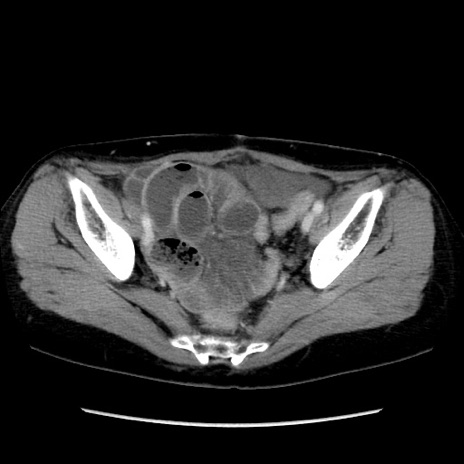

症例32(横断像)

【症例】40歳代 女性

【主訴】上腹部痛、嘔気・嘔吐

【現病歴】約9時間前頃から急に上腹部痛、嘔気、嘔吐が出現。改善しないため救急要請。

【既往歴】子宮頚癌(広汎子宮全摘術、放射線療法)、腸閉塞

【身体所見】腹部:平坦、軟、腸雑音亢進、上腹部を中心に腹部全体に圧痛あり。

【データ】WBC 8400、CRP 0.03